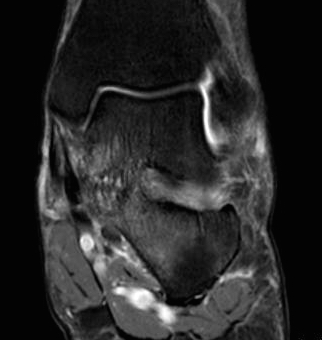

MRI

TC coalition middle facet